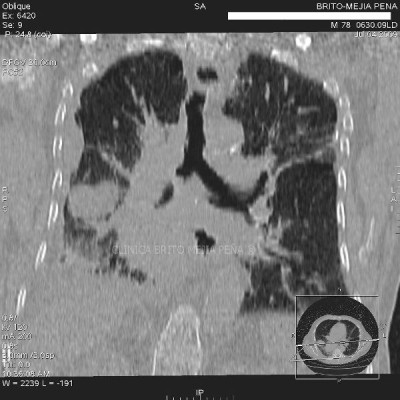

Hernia morgagni coronal